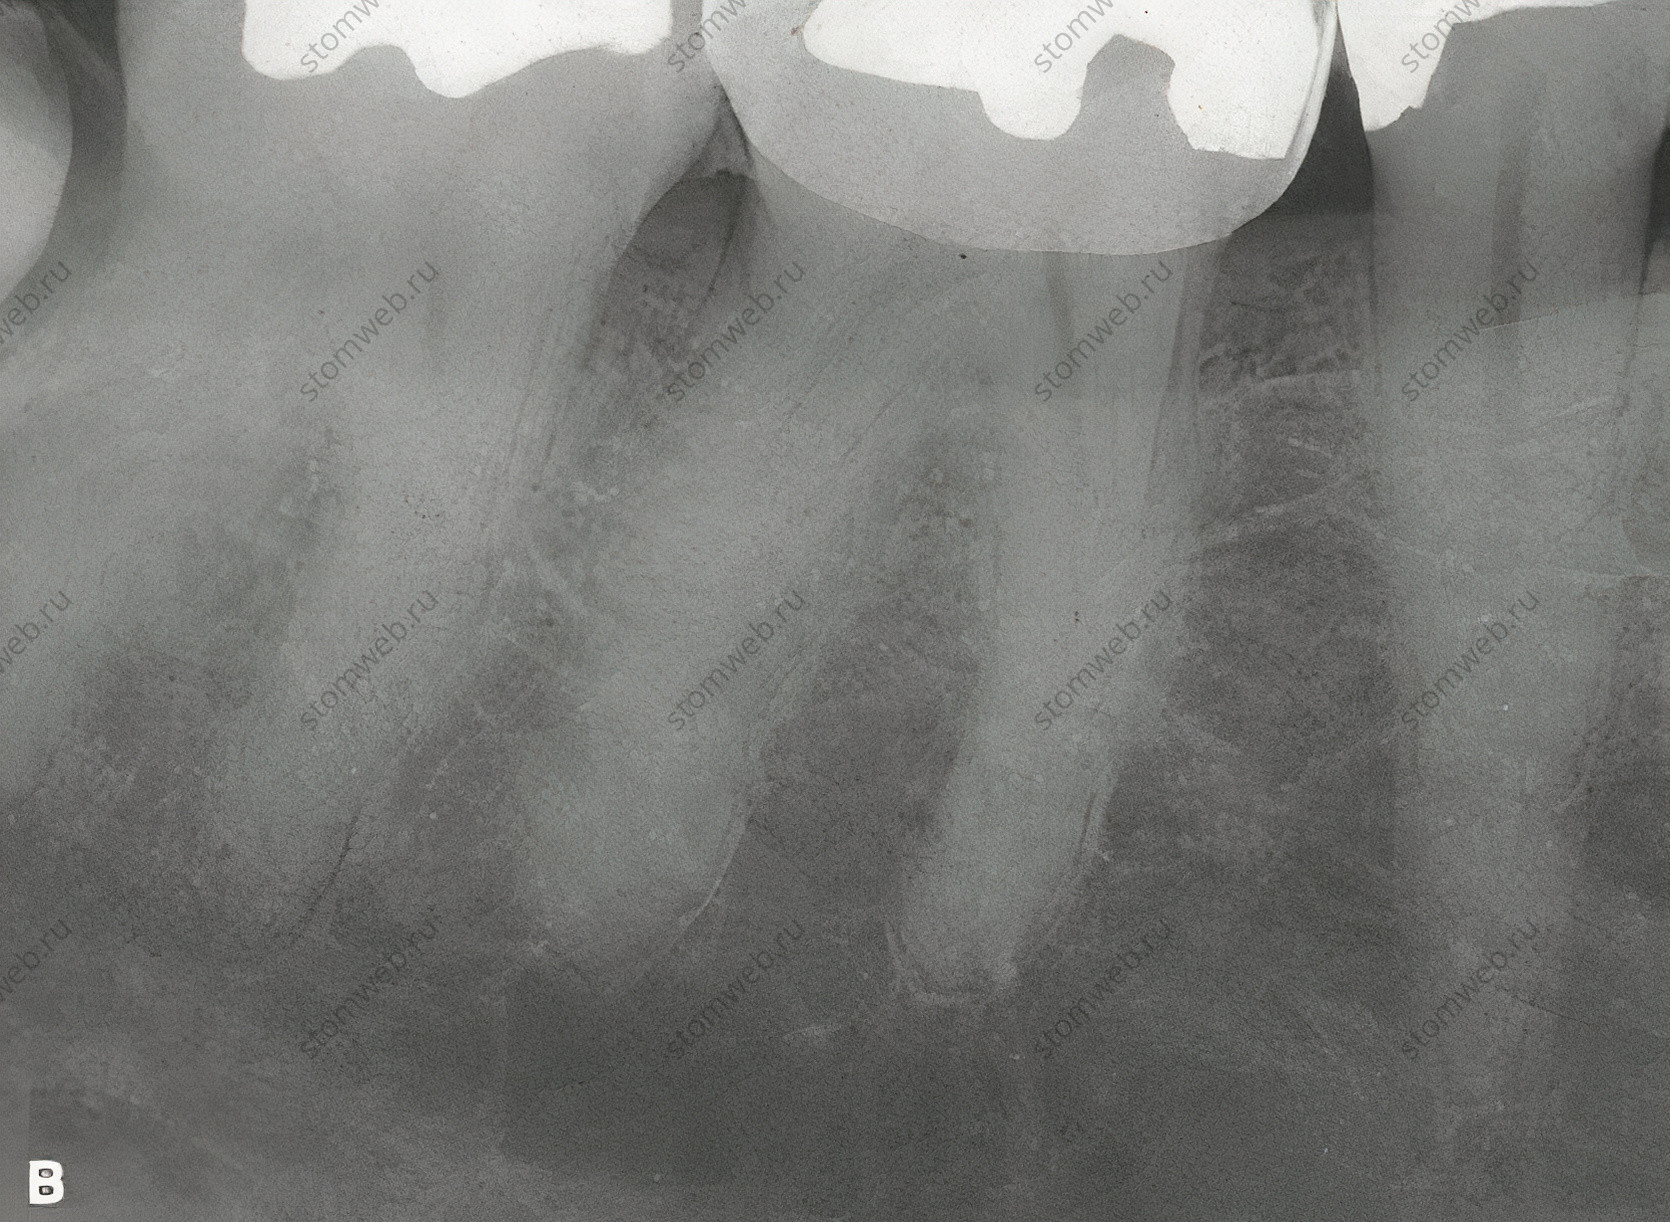

Рисунок 19 Диагностическое бандажирование зуба с трещиной коронки. A. Рентгенограмма первого моляра нижней челюсти с симптоматической трещиной коронки на дистальной стороне зуба. Поскольку линия перелома находится в мезио-дистальной ориентации, на снимке она не видна. Б. При диагностике (на основании симптомов и клинических данных) обратимого пульпита на зуб цементируют кольцо. C. Фотография сделана через 2 недели, когда пациент сообщает о полном отсутствии симптомов. Теперь пациенту может быть предложен вариант коронки с полным покрытием с информированием о том, что около 20% таких зубов могут потребовать эндодонтического лечения позже; некоторые пациенты могут предпочесть профилактическое лечение корневых каналов перед установкой коронки.